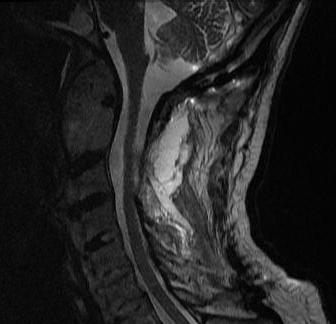

MRI